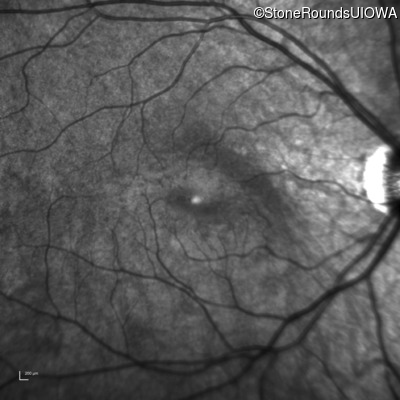

Infrared Fundus Photograph - Right - 20/40 +1

Exemplar